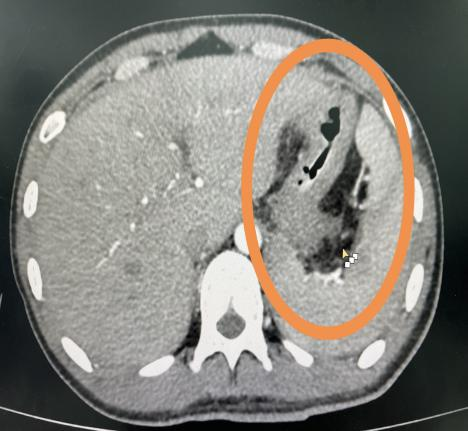

首先,对于某些特定部位的增强CT检查,如腹部或盆腔扫描,放射君在之前也和大家科普过,检查前的大量饮水能使胃肠道充盈,从而更好地区分各种腹部组织和器官。这种自然对比的效果,可以提高图像的对比度,使得潜在的问题区域更加突出,从而有助于医生作出更精确的诊断。

饮水前                                   饮水后